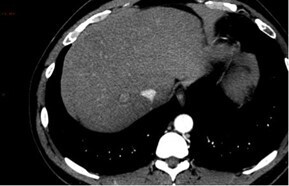

Question 11 - Sur ce scanner vous observez (une ou plusieurs réponses exactes) :

Le scanner retrouve de multiples masses intra-hépatiques infiltrantes. L’une d’entre elles, dans le segment V, est partiellement exophytique (bombant en sous-capsulaire) avec en son sein une flaque de produit de contraste. Par ailleurs, on retrouve une thrombose portale extensive de l’ensemble du système porte.

Au contact et le long de la gouttière pariéto-colique droite : un épanchement liquidien abondant, hétérogène, avec une composante spontanément hyperdense évocatrice de sang frais.

Le tout est donc évocateur, compte tenu par ailleurs des antériorités du patient, d’une progression de la maladie avec un CHC infiltrant bi-lobaire, rompu dans la cavité péritonéale avec saignement actif.